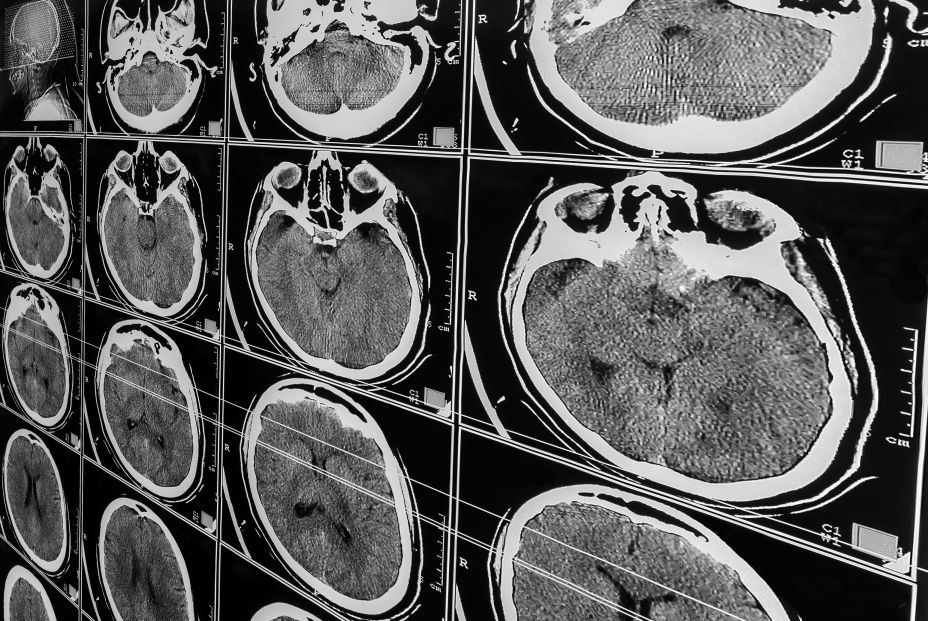

A diferencia de estudios previos, en la nueva investigación, los científicos de la Universidad de Medicina de Pittsburgh (EE.UU) liderados por Ariel Gildengers, profesor de Psiquiatría y autor de la misma, han implementado un ensayo controlado aleatorio (ECA), que incluye imágenes por resonancia magnética (IRM) humana de campo ultraalto (7T) de última generación, evaluación neurocognitiva y medición de biomarcadores basados en sangre y líquido cefalorraquídeo (LCR) para investigar el papel del litio como agente antidemencia.

En el nuevo estudio se asignaron aleatoriamente a 80 personas de 60 años o más con Deterioro Cognitivo Leve (DCL) para tomar carbonato de litio, a un nivel sanguíneo máximo tolerado (0,5 a 0,8 meq/L), o placebo durante dos años para evaluar los efectos del mismo en la preservación de la cognición y el retraso de la conversión a demencia. Los participantes recibieron una evaluación neurocognitiva anual, medición de biomarcadores en sangre y LCR, y una resonancia magnética de 7T de los volúmenes cerebrales estructurales (p. ej., hipocampo, gris cortical total).